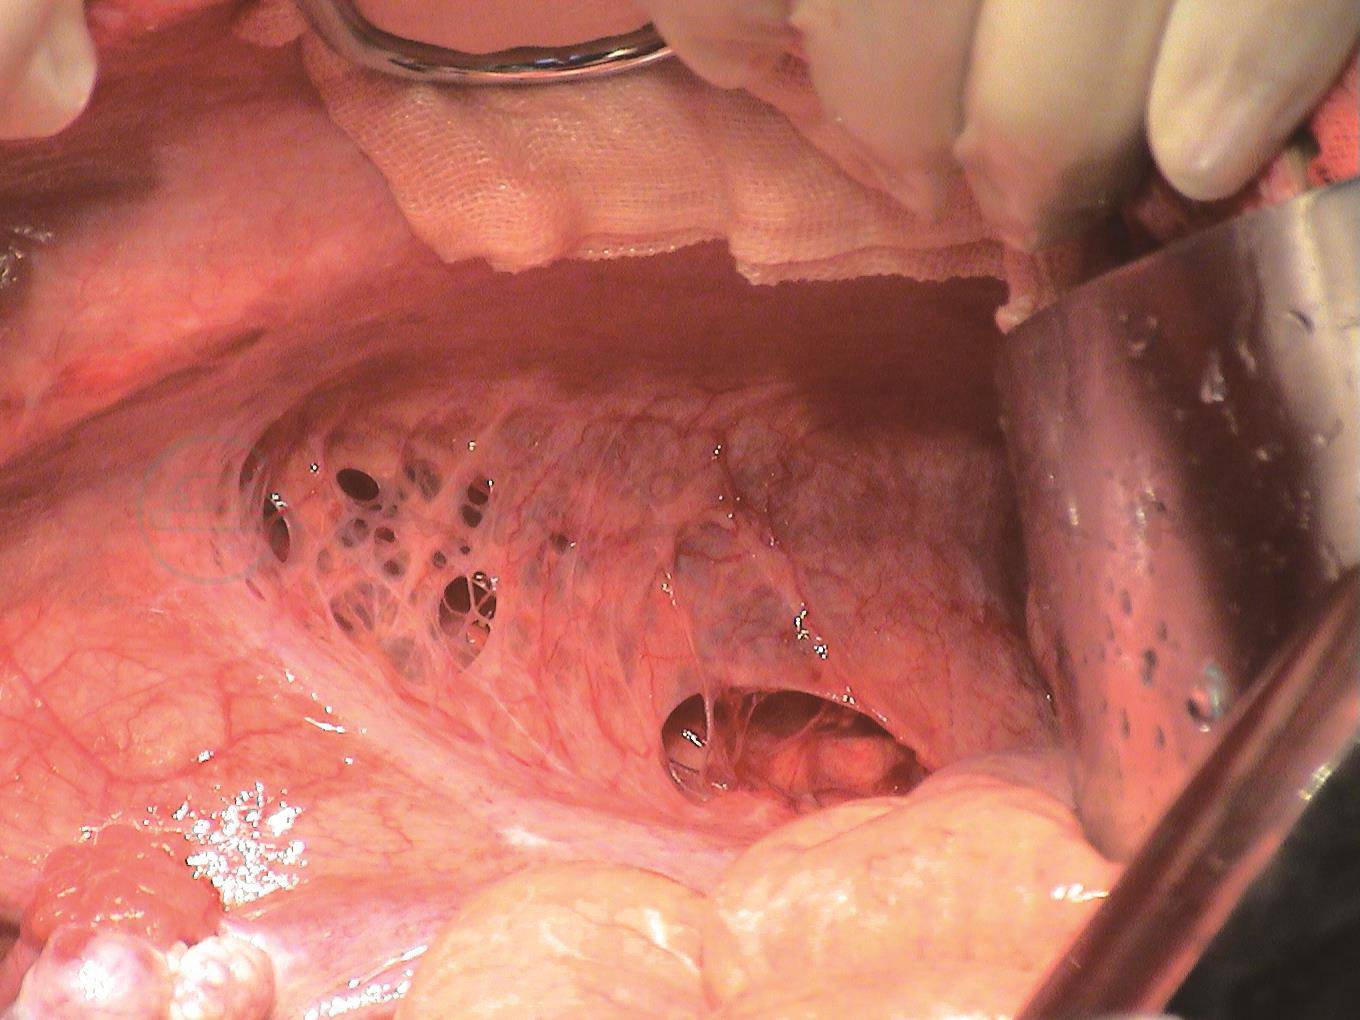

5.腹膜

腹膜缺损(图14)在乳糜性腹水的手术探查中可以见到,这是腹膜后淋巴管瘘乳糜液进入腹腔的途径之一。腹膜缺损可以是腹膜淋巴管囊肿破裂后的结果,也可能是原发性的。手术造成的乳糜性腹水,腹膜的损伤与腹膜后淋巴管的损伤以及乳糜性腹水,是序贯发生的。腹膜有吸收乳糜液的功能,这可以在乳糜性腹水的保守治疗中,乳糜液的实验室检查结果予以证实,重度的乳糜性腹水,腹膜的吸收功能受到严重影响。

图14术中照相显示腹膜缺损